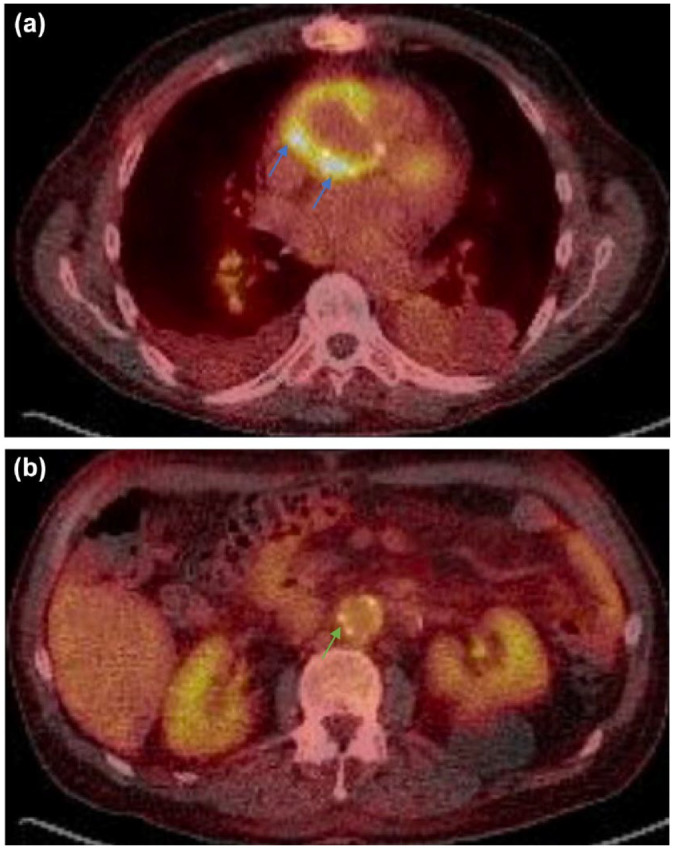

Infective endocarditis (IE) is an increasingly recognized condition with high morbidity. Patients with atypical symptoms, culture-negative infections, and prosthetic cardiac devices and implants represent challenging populations to evaluate and manage. Recent major society guidelines have recommended the appropriate incorporation of multimodality imaging in the evaluation of these more complex IE cases. This article draws on the available literature regarding the different cardiac imaging modalities and discusses the role of multimodality imaging in IE.